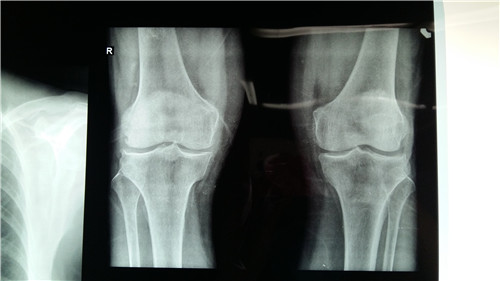

强直性脊柱炎被称为“不死的癌症”,已经到了谈强直色变的程度,很多患者在就诊称为强直性脊柱炎以后对生活失去了希望,除了脊柱,强直性脊柱炎还可能波及到髋关节等周围关节。会造成…「查看详情」

强直性脊柱炎是一种慢性炎症性疾病,累及脊柱、外周关节以及关节外组织。晚期可以出现脊柱强直,严重影响生活。合理的运动可以锻炼脊柱功能,延缓脊柱骨化和强直进展,对保持机体的功…「查看详情」

强直性脊柱炎在我国的发病率约为0.3%,以青少年多见。大量的临床资料已经证明,强直性脊柱炎除脊柱、关节受累外,还可以有心、肺、眼、肾脏和神经系统损害,虽然发生率很低,但病…「查看详情」